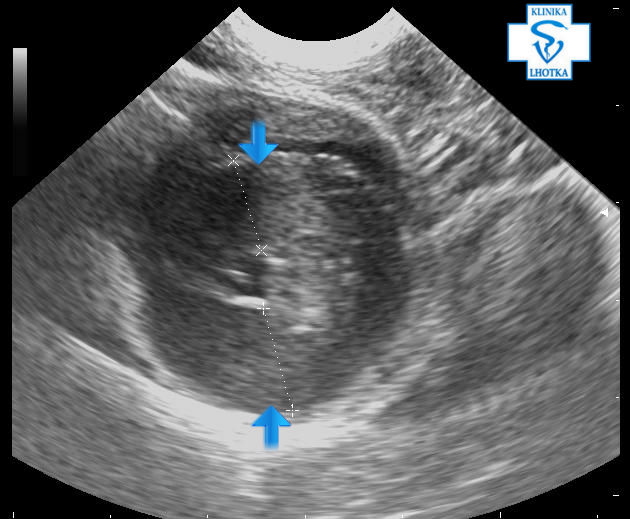

Na ultrasonografu  je možné „ztluštění“ srdeční svaloviny posoudit a změřit. Na podélném zobrazení srdce ukazují šipky na značně zbytnělou mezikomorovou přepážku a zadní stěnu levé komory:

Echokardiografie-HCM-dlouhá osa